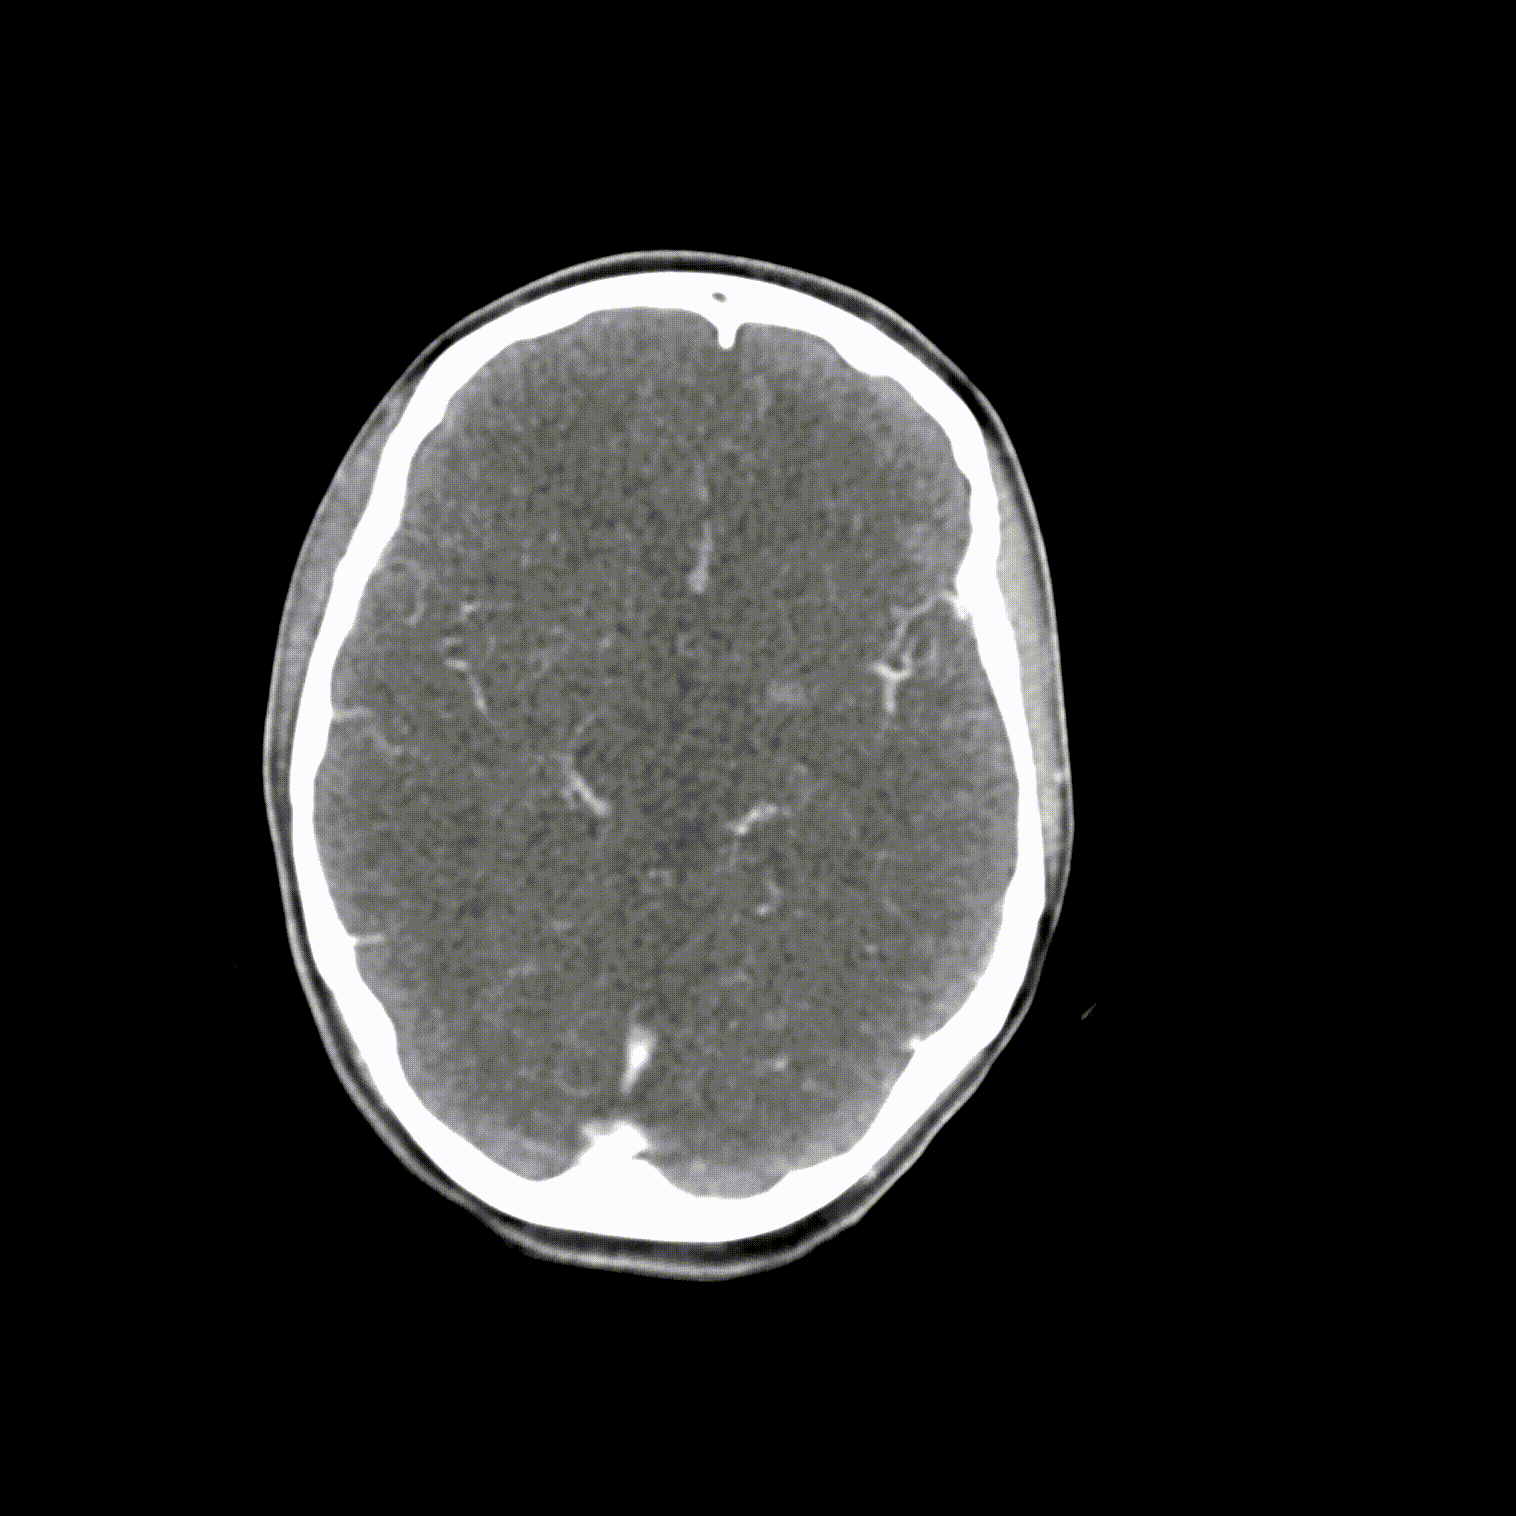

phantomX頭頸部模型,phantomX頭部模體是根據(jù) CT 數(shù)據(jù)制造的,包括所有組織的解剖細(xì)節(jié)。它經(jīng)過(guò)優(yōu)化,可在計(jì)算機(jī)斷層掃描中以 120 kVp 成像提供真實(shí)的衰減值,對(duì)應(yīng)于 73 keV 的平均光譜能量。可根據(jù)要求校準(zhǔn)其他光譜能量。

體模的尺寸和設(shè)計(jì)可能會(huì)發(fā)生細(xì)微變化。體??梢宰鳛橐患綌M人體?;蛞越孛嬖O(shè)計(jì)的形式提供。可以包括病理特征(例如,腫塊、血管病變)。